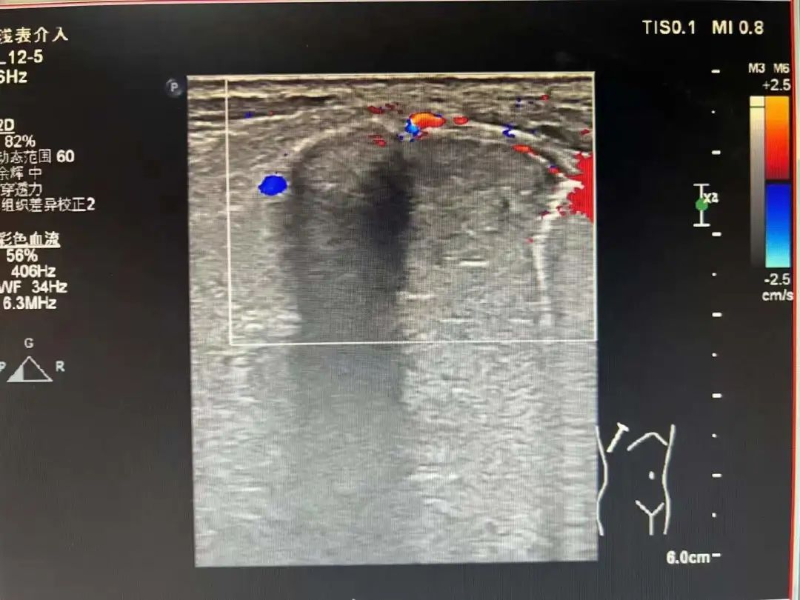

为进一步诊断病情,3月17日在陈勇辉超声引导下,超声医学科蒋朝霞主任医师为林伯伯进行肺肿瘤穿刺活检。超声引导下以右肺肿瘤最清楚处为目标,用穿刺针沿着引导线刺入,通过针尖穿越肿瘤触发活检枪进行活检。穿刺后,林伯伯无不适。我院超声医学科成功完成穿刺活检,为患者进行专科治疗做“最强辅助”,充分体现了我院超声医学科能力水平的综合提升,让患者能就近就医、就近诊断,为患者减轻看病就医经济负担和解决奔波劳碌的问题。

一是,方便快捷、安全性高、无辐射、伤口小、仅针眼大小的穿刺口,穿刺针在超声实时监视下精准活检,对正常人体组织破坏小,局部麻醉下完成,患者痛苦小,费用较低。